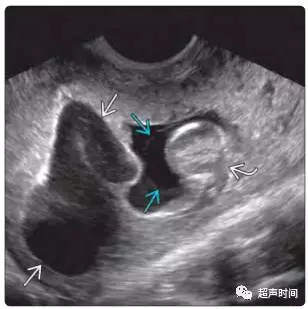

(3)分析血肿的回声性。若血肿逐渐吸收,体积缩小,则回声逐渐减低(图 4)。若为活动性或反复出血,血肿增大,血肿回声复杂,则提示病情加剧(图 5)。

图 5 反复出血导致血肿回声复杂,注意观察蓝色箭头和弯箭头所指的区别